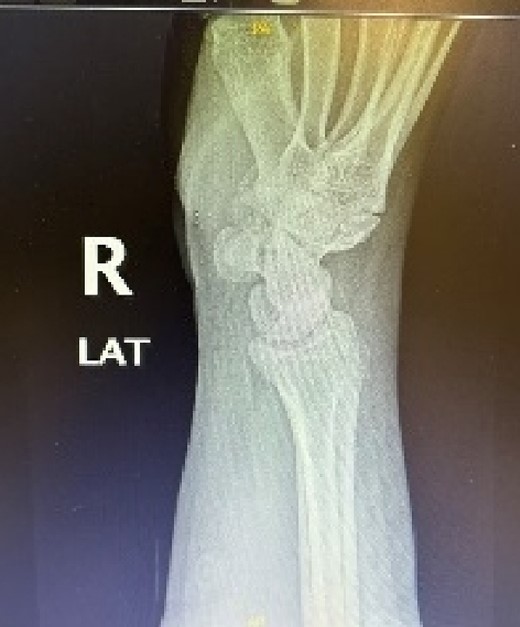

A 24-year-old male patient presented to the orthopedics clinic complaining of right-hand swelling for 2 years in the dorsal aspect of his hand described as ball like lesion. It started gradually over time without any triggering factors. However, in the last 6 months the patient has reported a mild on/off pain over the lesion that is dull aching aggravated with hand motion. However, the pain slightly declined with the use of analgesics. The pain was 3/10 in severity with some daily activity interruption with some range of motion (ROM) limitation. The patient had no constitutional, past medical, or surgical history with no significant family history. The patient has tried conservative management for 3 months but showed minimal improvement. Upon examination, there was right hand dorsal oval shaped swelling with no evidence of deformity, muscle wasting or overlying skin changes. On palpation, there was palpable lump noted over the second and third carpometacarpal joints ~1 cm in diameter that is well circumscribed, soft in consistency, and mobile. The lump is palpated over and surrounded by an underlying hard bony protuberance with mild tenderness (Fig. 1). The right hand and wrist range of motion showed 5–10 ° flexion and extension limitation of wrist motion with accompanying pain and second and third CMC joints with no affection of any other movements. Furthermore, the piano, distal radioulnar joint squeeze, Watson tests and neurovascular examination, extensor tendons examination were unremarkable. In the meantime, a ganglion cystic lesion was suspected with and underlying bony lesion. Meanwhile, his laboratory investigations were unremarkable. Hand and wrist X-rays were obtained and showed osteophyte formation in the base of the second and third metatarsal and distal aspect of the capitate and trapezoid with joint space narrowing consistent with carpal boss lesion (Fig. 2). Hand and Wrist Ultrasonography also performed showed well defined subcutaneous cystic lesion measuring about 7 × 2 mm consistent with ganglion cyst seen in between related bony prominence. Following that, the patient underwent an open excision of the carpal boss, and ganglion lesions. Intra-operatively, through the dorsal wrist approach over the quadrangular joint of the wrist, the retinaculum and extensor compartments were incised until soft oval ganglion cyst measuring about 0.5 cm in diameter was found and excised (Fig. 3). Upon further exposure, irregular shaped bony overgrowth ~1 cm in diameter was noticed underlying the cystic lesion (Fig. 4). The lesion and its surrounding sclerosis excised using wedge excision technique using osteotomes and ronjour while avoiding injuring the intra-articular cartilages (Fig. 4). Histopathology of the lesions revealed a cystic lesion with flbro-collagenous cyst wall with fragments of benign mature bone with overlying fibrous tissue, no mature Hyaline cartilage component is seen, and the medullary cavity contains fat and hematopoietic marrow. Postoperatively, the patient had no neurovascular compromise. X-rays were obtained and showed flattening of either sides of the quadrangular joint of the wrist with an adequate excision of the bony outgrowth. The patient was followed 2 weeks later in which stitches were removed and instructed on rehabilitation. Upon 2 months follow up, the patient had no complaints. Upon examination, there is no lesion that can be inspected or palpated with no tenderness with healed surgical scar. Also, the patient showed no pain and limitation of hand and wrist range of motion with intact extensor tendons and CMC ligamentous functions (Fig. 5). Six months postoperatively, the patient was symptoms free. The scar showed healthy tissue. Hand and Wrists examinations showed no limitation. X-rays showed no evidence of re-growth or degenerative changes. Eventually, the patient reported that his quality of life had improved significantly, especially in terms of pain, and range of motion with no disturbance in hand and wrist functions and he was very happy with the results. This case has been reported in line with the Surgical Case Report (SCARE 2020) [7].